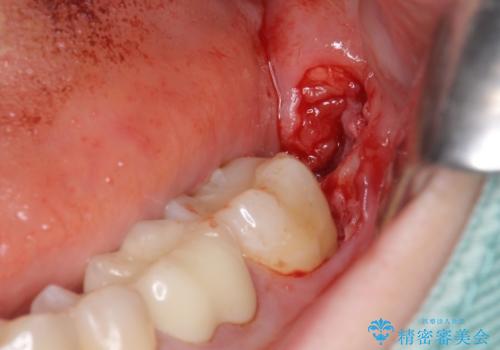

ただし、元のインレーが遠心マージンが縁下だったため、矯正治療後に歯ぐきの厚みを減らして、しっかり歯ぐきの上にマージンラインが来るように整える手術(ディスタルウェッジ)を行いました。

レーザーや電気メスで分厚い歯肉を焼いても一時的で、やがてまた元のように歯ぐきが上まで増殖しますので、今回は骨の厚みも調整し、7番の遠心を出来るだけ下げました。